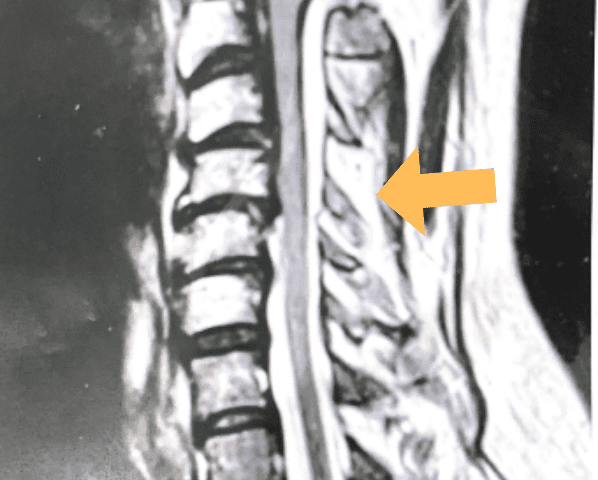

(2a) Lateral Flexion cervical x-rays demonstrating 8mm of splaying of the C34 interspinous distance

(2b) Lateral Flexion cervical x-rays extension image demonstrating 8mm of splaying of the C34 interspinous distance.

The fluid was possibly consistent with CSF versus chronic hematoma. The patient was also noted to have a high signal within the interspinous space of C3-C4. This high signal was consistent with a ruptured C3-4 interspinous ligament. Cervical flexion-extension x-rays demonstrated 6 mm of widening of the C3-4 interspinous space on flexion x-ray consistent with cervical instability (Fig. 2a and 2b).